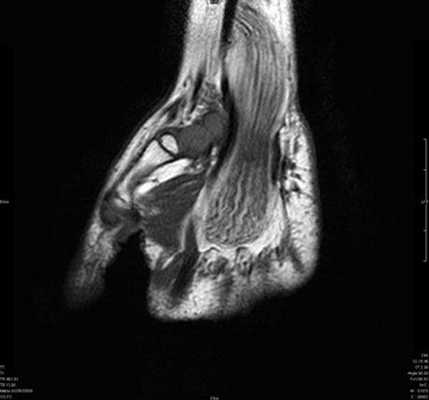

Клинически: Острая боль. В анамнезе нет травмы или чрезмерной нагрузки. Увеличение диаметра и повышение МР-сигнала в проекции сухожилия разгибателя.

Синдром повреждения сухожилий

Синдром повреждения сухожилий включают частичные и полные их разрывы, проявления теносиновита и посттравматического тендиноза. Основную долю составляют теносиновиты, возникающие изолированно или на фоне повреждения костей и связок. Морфологически теносиновиты характеризуются скоплением синовиальной жидкости под оболочками сухожилия. Рентгенодиагностика в диагностике теносиновитов неинформативна. Наиболее информативны в диагностике теносиновита УЗИ и МРТ.

Теносиновит сухожилий глубокого сгибателя пальцев кисти и длинного сгибателя большого пальца.